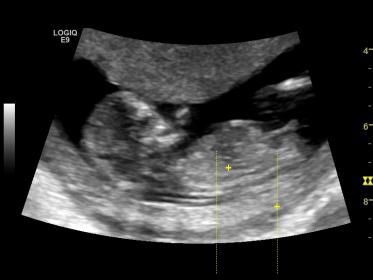

Update at 13.5 weeks

I originally posted my 12.4 week nuchal scan, I had to have this redone due to results indicating high risk for trisomy 21. Just seeing what people's opinions are based on this latest ultrasound :)

Thanks in advance Attachment 22542Attachment 22542